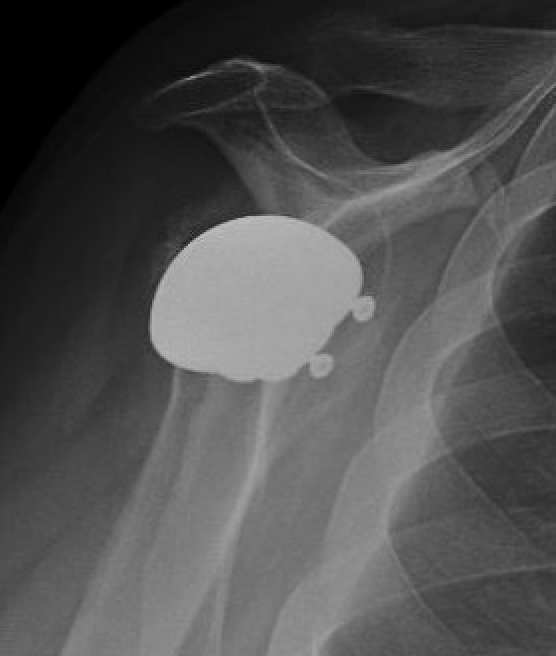

Xray

Signs of chronic shoulder dislocation

Chronic shoulder dislocation with large Hill Sachs and minimal glenoid deficiency

Chronic shoulder dislocation with large Hill Sachs and significant glenoid deficiency